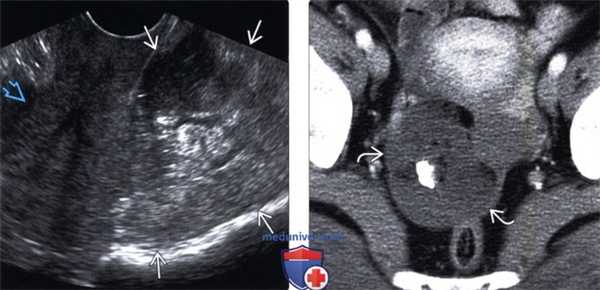

(Слева) Трансвагинальная ультрасонография: отмечается, что дермоид может иметь нехарактерную картину визуализации на ультрасонографии при условии, что мягкотканный компонент будет преобладать над жировым. Данный дермоид гетерогенно эхогенный и заполняет замкнутое пространство кзади от матки.

(Справа) КТ с контрастированием того же образования, аксиальный срез: определяется относительно небольшое количество жира с преимущественно мягкотканным компонентом, что формирует специфичную картину визуализации на ультрасонографии.

(Слева) На МРТ Т1 дермоид имеет гиперинтенсивный внутренний сигнал, который представляет собой скопление жира.

(Справа) КТ с контрастированием того же дермоида, аксиальный срез: определяется кальцинированный зуб, который обнаруживается в 1/3 случаев. Обратите внимание, что жир в дермоиде заметно гиподенсивнее по сравнению с внебрюшинным жиром.